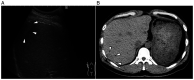

Intrahepatic splenosis (IHS) is a rare disease that is considered to result from heterotopic autotransplantation or implantation of splenic tissue after splenic trauma or surgery. A 46-year-old man with a treatment history of a left lateral liver segmentectomy and splenectomy for a road traffic injury 30 years earlier presented to Sakai City Medical Center (Sakai, Japan) with acute abdominal pain in November 2019. Physical examination showed no significant signs, and serum data were normal. Computed tomography revealed a hypodense mass measuring 2.5x1.7 cm in segment 7 of the liver. Gadoxetic acid-enhanced magnetic resonance imaging showed early enhancement in the arterial phase and washout in the delayed phase. Therefore, laparoscopic surgery was performed with a preoperative diagnosis of hepatocellular carcinoma. Pathological examination of the tumor showed IHS. The postoperative course was uneventful, and the patient developed no new abnormal region in the liver during 2 years of follow-up. The present study presented a case of IHS assumed to be hepatocellular carcinoma. IHS should be considered as a differential diagnosis of a liver mass detected years after splenic trauma or surgery, even in cases with imaging patterns suggesting malignancy.